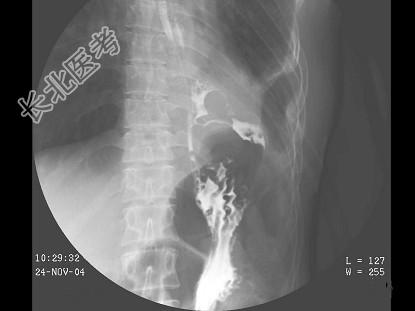

- 单项选择题女,39岁, 左下肺叶切除术后。体检:左下肺呼吸音弱, 行胸腔闭式引流术,引流出脓性分泌物。结合图像, 最可能的诊断为 ( )

E、食管下段胸腔瘘